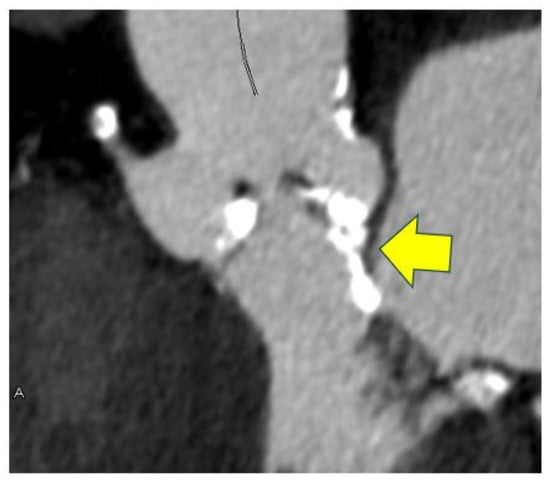

- Saito, Y.; Takaoka, H.; Funabashi, N.; Ozawa, K.; Tamura, Y.; Saito, M.; Matsumiya, G.; Kobayashi, Y. A case of very severe aortic stenosis due to unicuspid aortic valve mimicking bicuspid aortic valve with calcification on cardiac computed tomography. Int. J. Cardiol. 2016, 215, 516–518. [Google Scholar] [CrossRef]